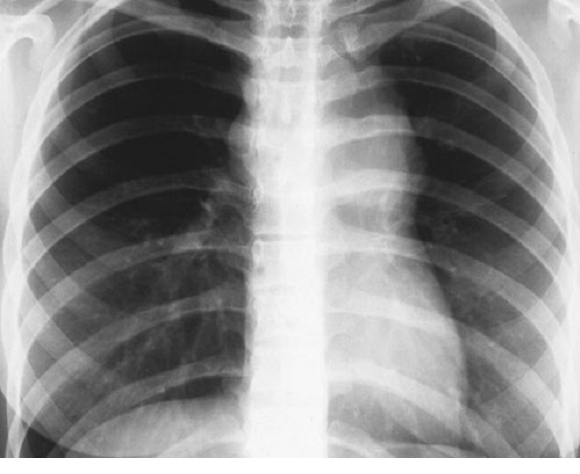

- Neumomediastino observado en un accidente leve de sobreexpansión pulmonar sin sintomatología neurológica pero con enfisema subcutáneo importante. Observese la fina silueta que delimita y perfila la sombra cardiaca. (Dr. Desola).